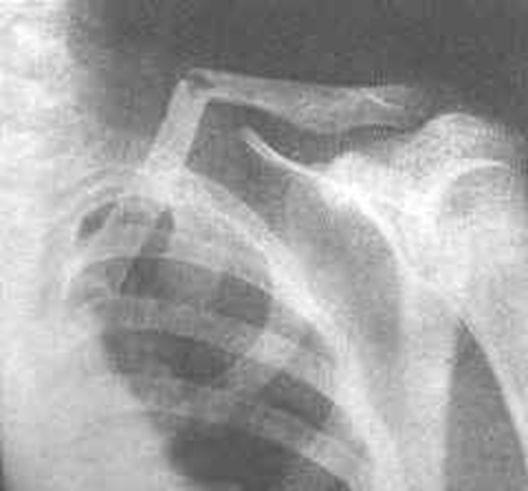

正常肩关节